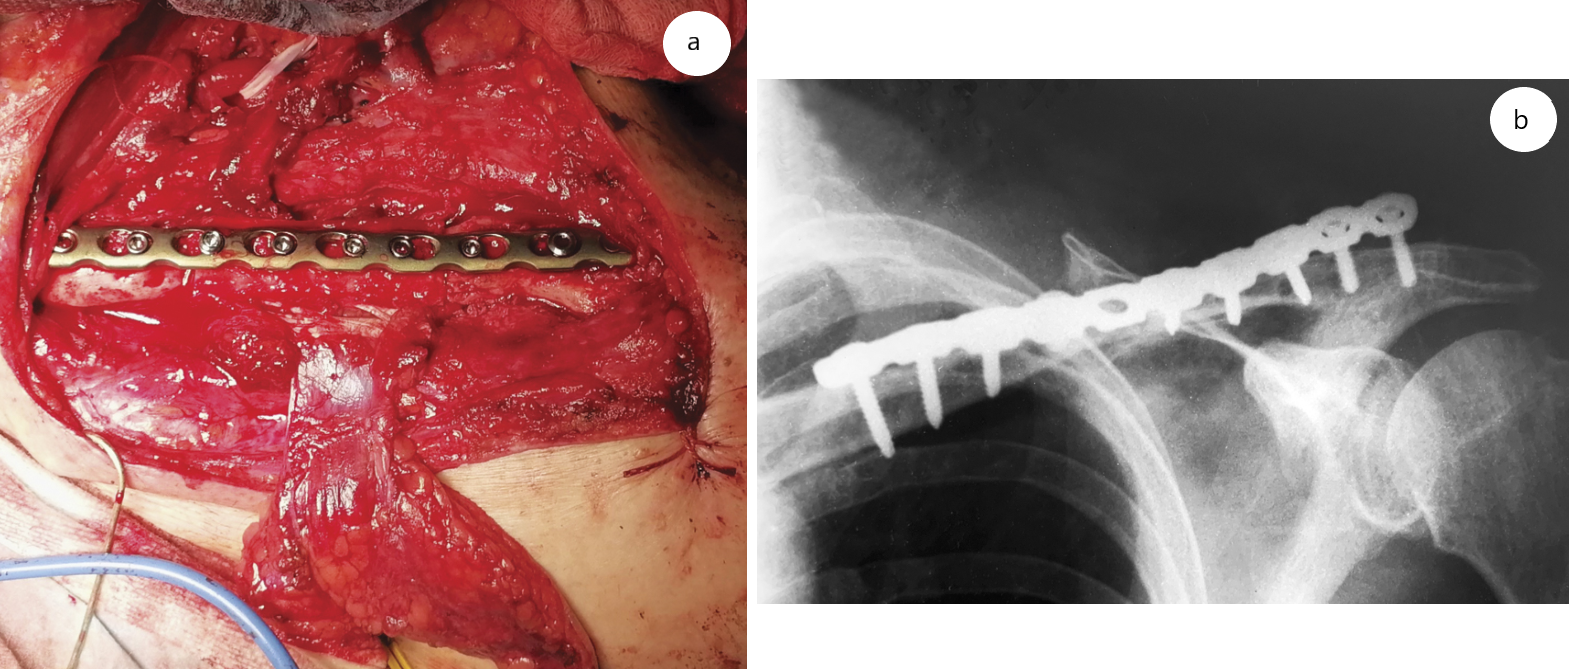

Параллельно верхнему краю ключицы выполнен разрез длиной 15 см, из которого удалена металлоконструкция. Иссечен рубец, выполнена резекция концов отломков до появления «кровяной росы», при этом сформировался диастаз на протяжении 4,5 см. Из S-образного разреза вдоль заднего края кивательной мышцы выделены реципиентные сосуды a. et v. transversus colli (рис. 4). Пульсация артерии состоятельна, вена функционировала на видимом протяжении.

Рис. 4. Комбинированный доступ к ключице

После маркировки под контролем УЗИ при помощи ручного УЗ-доплера перфорантных сосудов классическим передним доступом сформирован лоскут с сохранением a. et v. tibialis anterior и n. fibularis profundus. Выполнена двойная остеотомия малоберцовой кости (на 6 см ниже головки малоберцовой кости и на 6 см выше латеральной лодыжки). После выделения и перевязки дистального участка a. et v. peroneus мобилизован трансплантируемый фрагмент кости вместе с мышечной манжетой из m. flexor hallucis longus и m. tibialis posterior. Перонеальный сосудистый пучок выделен и отсечен у бифуркации с задними большеберцовыми сосудами. Произведена адаптация костно-мышечно-кожного лоскута в зоне дефекта, при этом имплантировано 5,2 см кости для создания эффекта «распорки» с умеренной компрессией на стыках с концами матричных фрагментов. Отломки фиксированы реконструктивной пластиной с угловой стабильностью. Анастомозы сосудов лоскута с a. et v. transversa colli выполнены по типу «конец-в-конец» (рис. 5). Пуск кровотока — без особенностей, отмечены кровоточивость кости и мышечной манжеты, а также убедительные признаки кровообращения в сигнальной кожной площадке.

Рис. 5. Вид раны на завершающем этапе операции (а) и контрольная рентгенограмма (b)